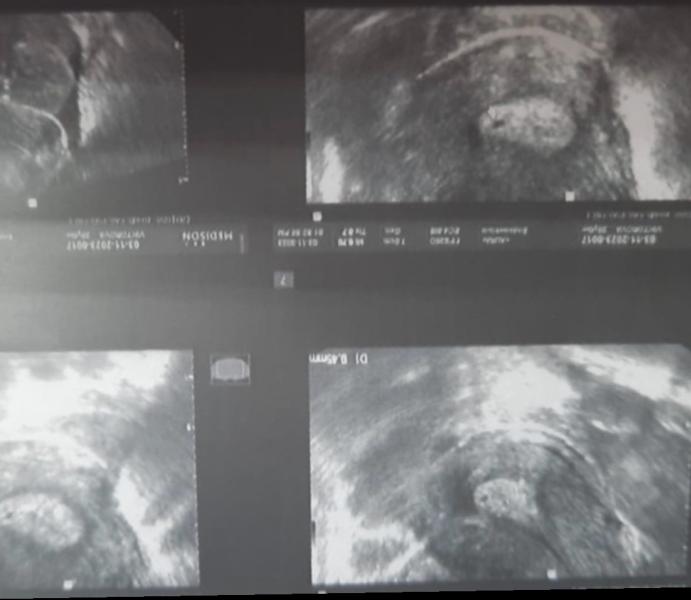

В августе пациентка обратилась на онлайн консультацию по поводу планирования беременности. И вот вчера она обращается ко мне с результатами узи в страхе, почему доктор не уверен в беременности. Почему у нее задержка, но не виден эмбрион. А задержка всего лишь пару дней. Так вот, в первую очередь важно сдать ХГЧ, оценить его рост так же повторно через два дня. А дальше в случае если ХГЧ был был выше 1000-1500 отправляться на УЗИ. Либо идти на узи через 2 недели от задержки. На узи картине формир...